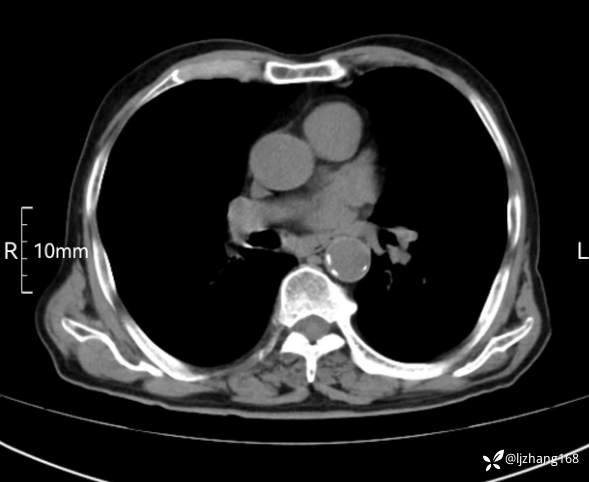

辅助检查:胸部CT:双肺肺气肿,间质性病变,血气分析:PH 7.413, PCO2 29.2mmHg, PO2,81.8mmHg,乳酸 3.3mmol/1,剩余碱-4.0mmol/1,HC03 18.8mmol/1。全血超敏C反应蛋白:超敏C反应蛋白 135.60 mg/L、 白细胞 14x19^9/L,中性粒细胞11.6x10^9/L。